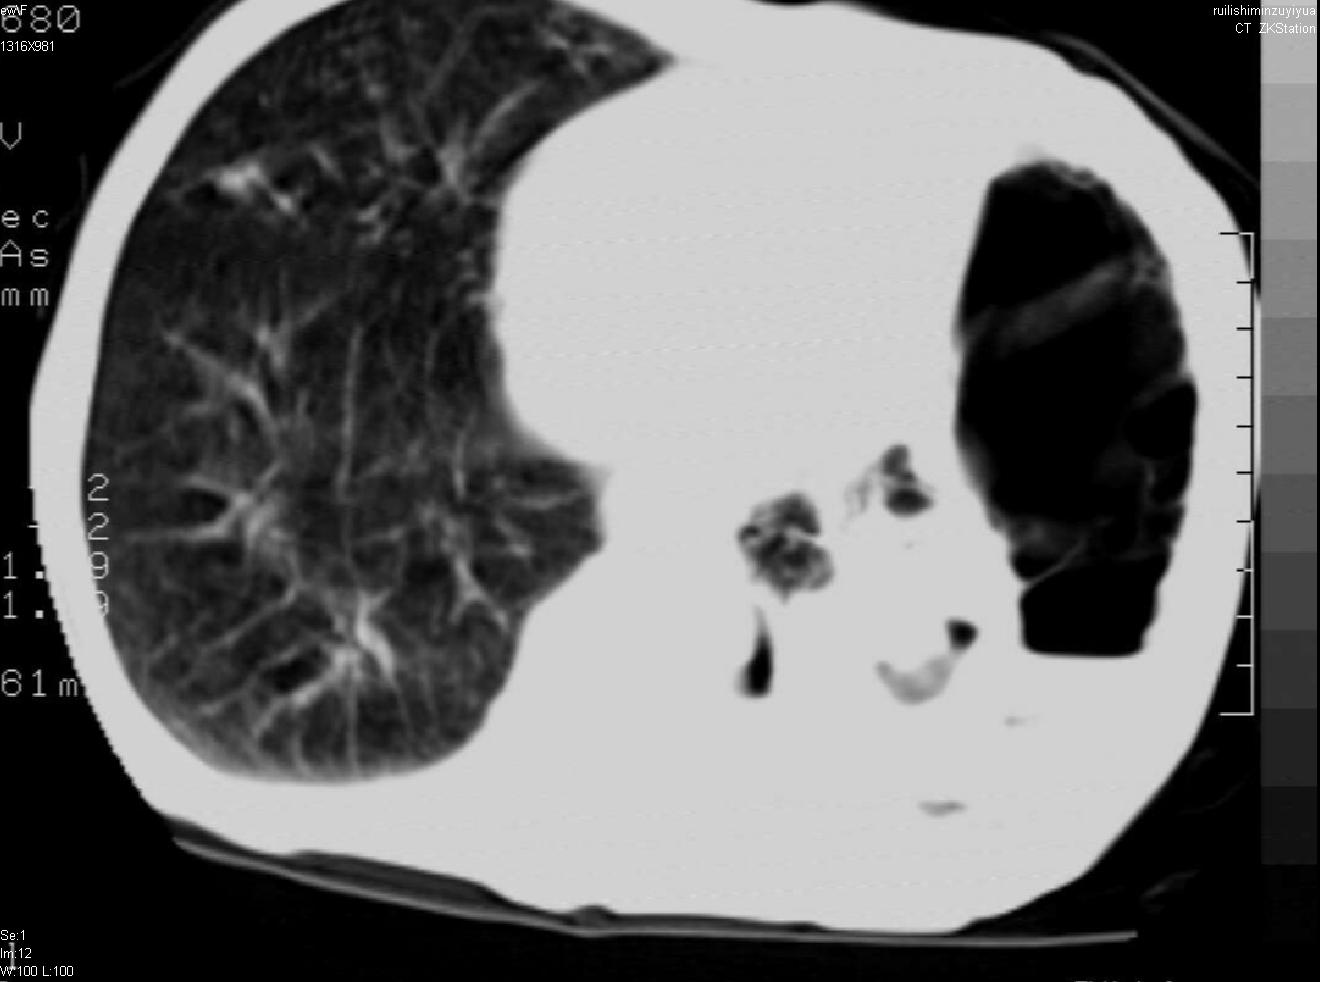

以下是引用天南地北在2007-6-11 23:32:00的发言:[br]1:左侧肺毁损(结核性)伴感染(多发空洞伴液平面)。[br]2:右肺继发型肺结核。

以下是引用avril在2007-6-12 1:17:00的发言:[br]1、左肺毁损。[br]2、左肺多发肺大泡伴自发性气液胸形成。[br]3、右肺继发型结核。

以下是引用尚峰在2007-6-11 22:44:00的发言:[br]慢阻肺、肺纤维化、肺大泡、气胸形成,此患者有没有急性病史?